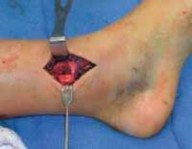

2. For a medially gapped Salter Harris type II abduction injury, a medial approach is used (

TECH FIG 1

).

A B CTECH FIG 1•

Surgical approach to a medially gapped fracture.

A.

This AP radiograph demonstrates a medially gapped Salter-Harris type II abduction-type fracture.

B.

A medial approach is used to obtain open reduction of this fracture.

C.

This operative photograph highlights the periosteum interposed in the physeal fracture, which was extracted to obtain anatomic reduction and prevent medial gapping.